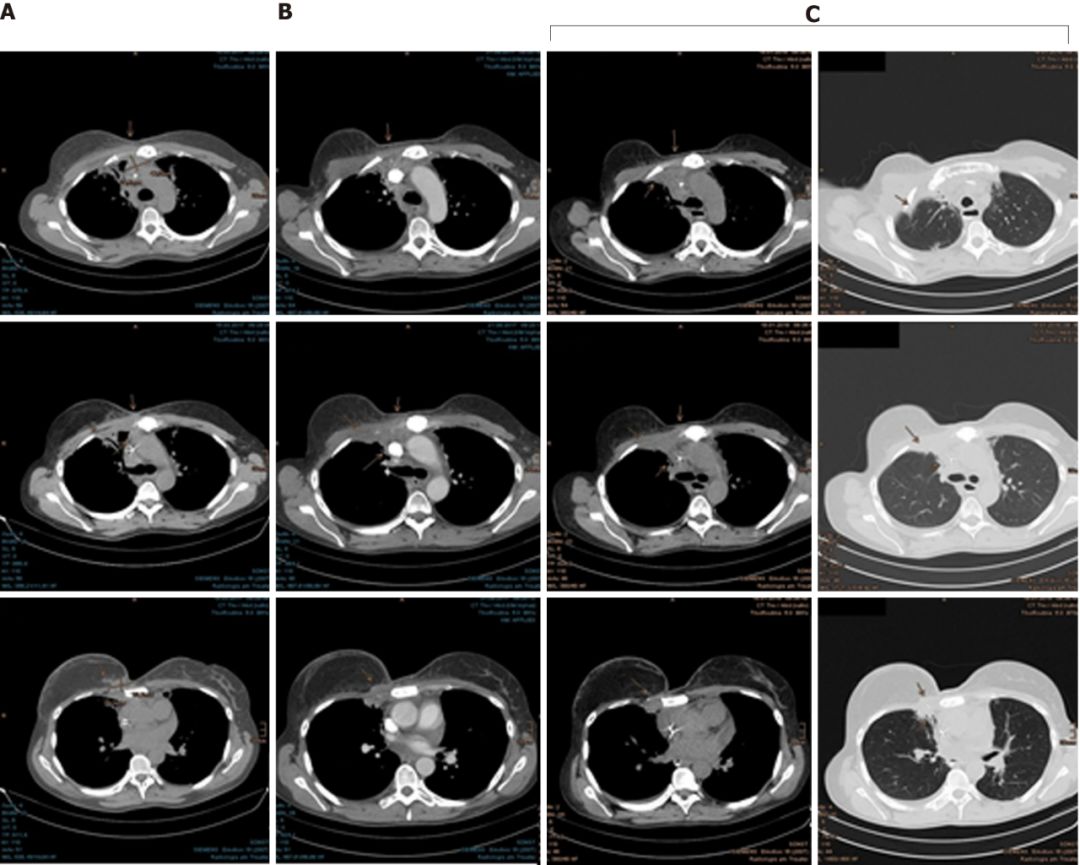

2015年7月,CT扫描发现肿瘤已经侵入肋软骨和腹侧胸膜,她的癌症全面复发了。

这时,Mary已经没有更多的选择,为了降低体内雌激素水平,她切除了双侧卵巢,然后参加了一项氟维司群联合ribociclib的临床试验。2016年2月,由于病情进展,她退出了试验,右侧胸骨的病灶已经达到了30 mm×50 mm×20 mm。

2016年11月至12月,Mary接受了右侧胸骨肿瘤以及邻近胸膜,右侧腋窝,胸骨旁和纵隔区域的淋巴结转移的质子放疗。

幸运的是,Mary对质子治疗的耐受性很好,仅出现了轻微的咳嗽和反流。由于对肺部有一定的辐射剂量,她吃了一些环丙沙星预防放射性肺炎的发生。随后的检查结果显示,癌细胞终于耐不住质子的强烈攻击,开始节节败退,病灶在一次次的缩小。

在最近一次CT扫描中,仍然没有发现肿瘤进展迹象。为了预防病情进展,Mary现在继续使用来曲唑和denosumab进行全身治疗。